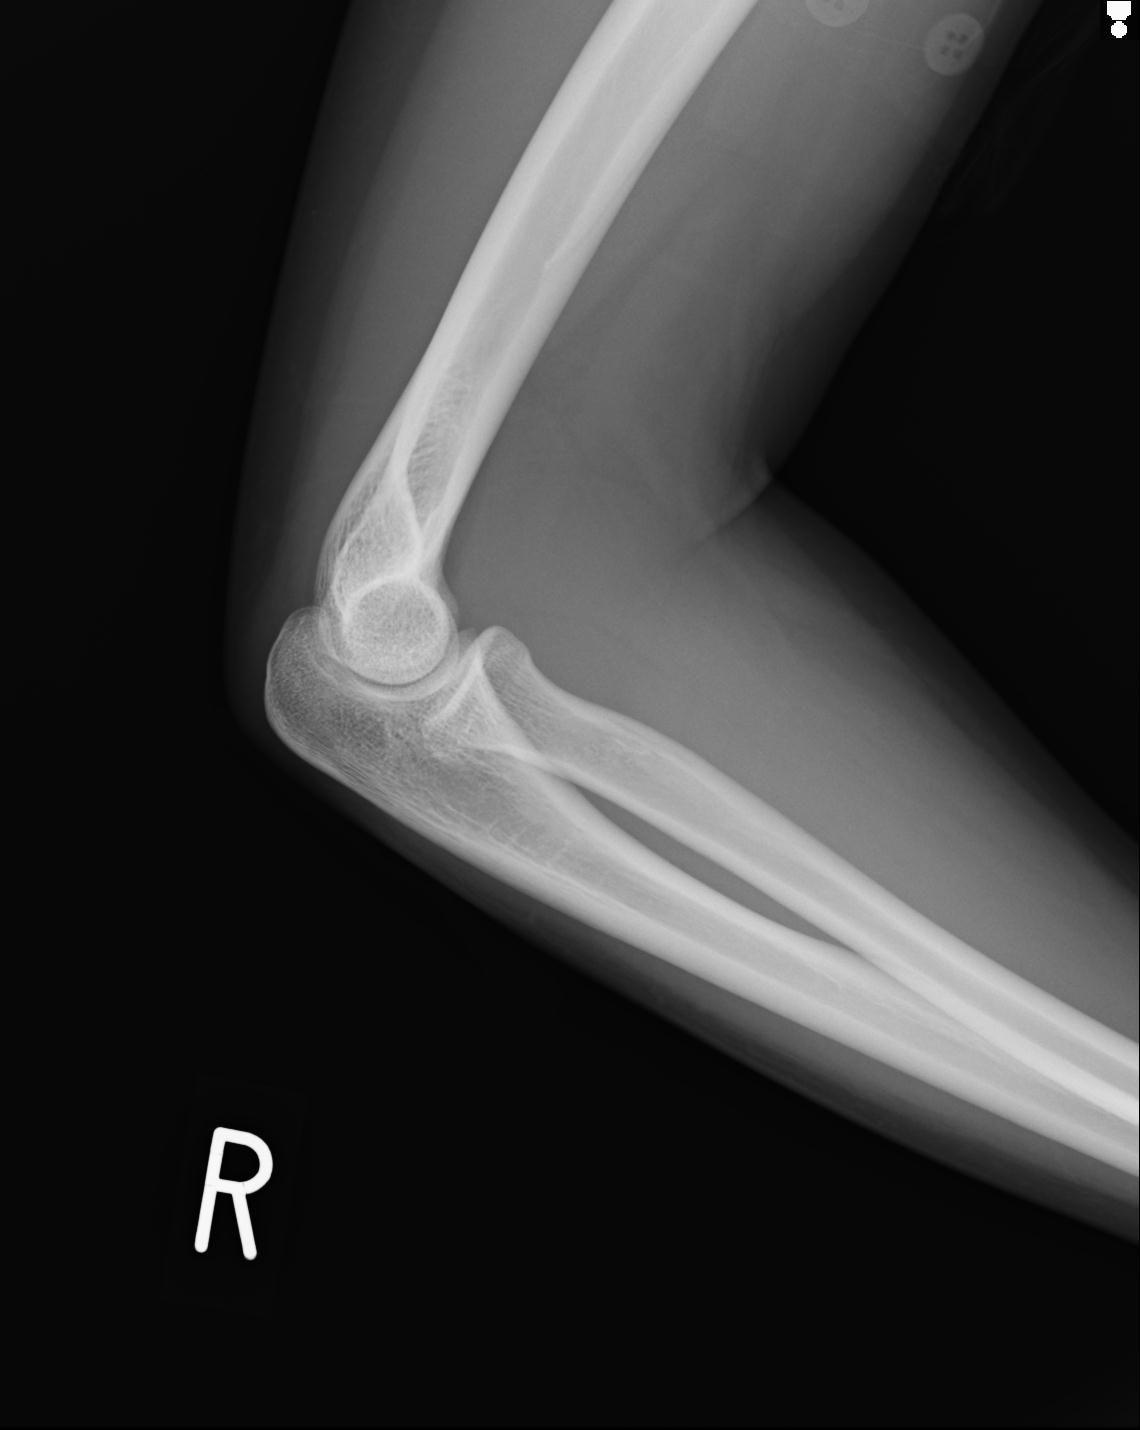

2271 1/25 右肘 4R 1/27 4R 3/24 4R 94歳女性 右通顆骨折